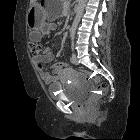

CT

A heterogeneous mass as with ultrasound. Its relationship to other pelvic organs is delineated, in particular, to review for local invasion.

Used to assess for locoregional lymphadenopathy and distant metastatic disease in the lungs, liver and bones.